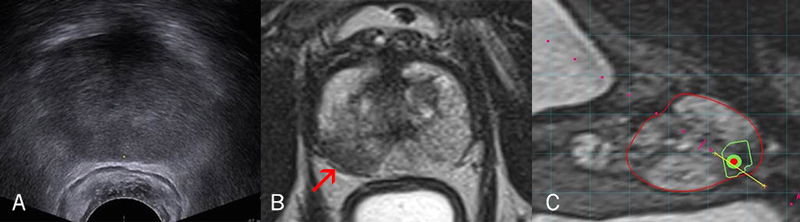

Una ecografía de la próstata (A) no proporciona información tan detallada como una resonancia magnética nuclear (MRI, por sus siglas en inglés) (B). La MRI revela un área oscura (flecha) que sugiere la presencia de un tumor. Al fusionarse las imágenes obtenidas mediante MRI y ecografía (C), el cirujano tiene un panorama aún más claro de la zona donde realizar la biopsia. La próstata está delineada en rojo, el tumor sospechoso en verde y la aguja de la biopsia en amarillo.

Para los hombres con PSA elevado con o sin biopsia previa, los urólogos de Cleveland Clinic están utilizando una nueva tecnología para detectar el cáncer de próstata. El método se denomina biopsia guiada por fusión y utiliza el poder de las imágenes de la próstata obtenidas mediante MRI multiparamétrica de alta resolución junto a la biopsia de próstata guiada por ecografía en tiempo real para lograr una biopsia focalizada precisa de las áreas sospechosas de la próstata que pueden albergar un cáncer de próstata agresivo. Combina el poder y el detalle de la MRI con la conveniencia de realizar la ecografía en tiempo real.

A continuación se indica cómo funciona: Primero el paciente se somete a una MRI especializada de alta resolución, que es eficaz para identificar áreas sospechosas en la próstata que pueden ser cancerosas. Posteriormente, en un entorno ambulatorio, el urólogo inserta una sonda ecográfica en el recto del paciente para examinar la próstata. Un software especial “fusiona” las imágenes de la MRI anterior con las imágenes de la ecografía en vivo. El resultado es una imagen tridimensional altamente detallada de la próstata, en la que se resalta el área sospechosa para que, de esta manera, se pueda posicionar una aguja de biopsia de forma precisa para obtener una muestra para analizar.